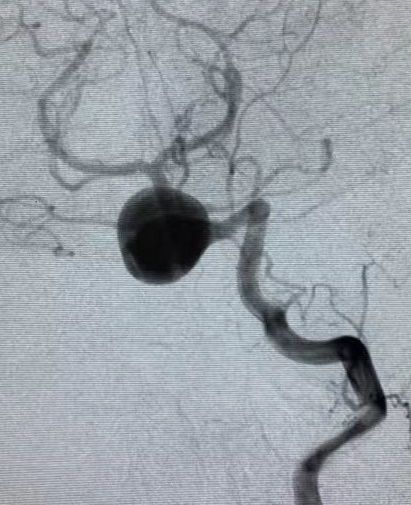

陈世琴,女,28岁

主诉:间断头痛2月余

现病史:2月前无明显诱因出现头痛,呈进行性加重,无恶心及呕吐,无肢体活动障碍,曾就诊于当地医院查头CTA及MRA示:椎-基底动脉汇合部巨大动脉瘤。双侧椎动脉均有供血,以左侧为主。

患者核磁共振显示脑桥-延髓前方流空影,考虑动脉瘤,有明显的双腔征,瘤壁有加强,且对脑干有一定的压迫。

经左椎动脉造影可见椎-基底动脉汇合部巨大动脉瘤,双侧椎动脉均有累及,以左侧椎动脉为主,右侧PICA与动脉瘤有一定距离,基底动脉稍受累及,AICA距离动脉瘤较近。